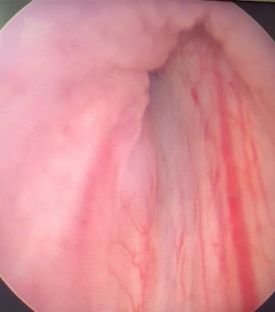

Prostate surgery

Prostate problems are not uncommon, and they affect a significant number of men worldwide.